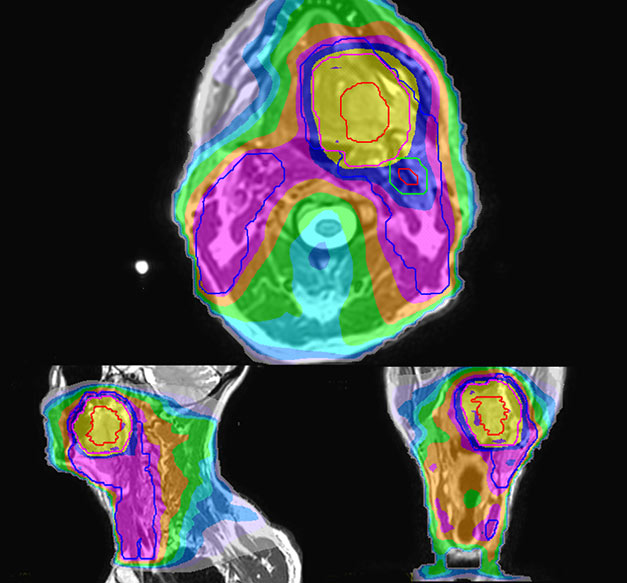

MR-based contouring and planning

MRCAT is primary image dataset for dose calculation (left).

3D T2W TSE MRI with 36 cm Field-of-View is used for delineation of prostate and organs at risk (right).